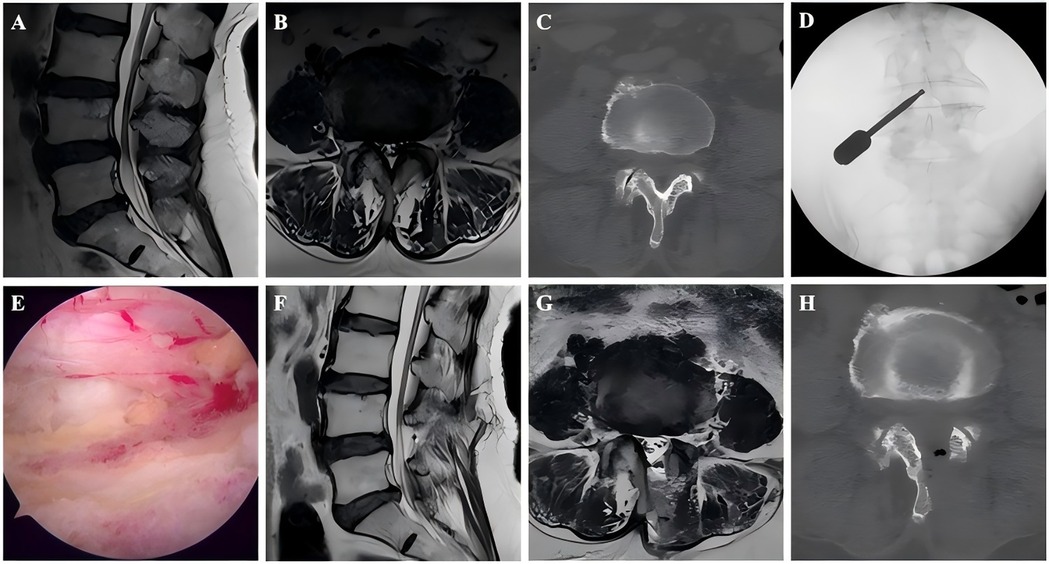

Background: Unilateral biportal endoscopy (UBE) is an important minimally invasive surgical treatment option for lumbar spinal stenosis (LSS). However, to our knowledge, no studies have focused on UBE for treating adjacent segment disease (ASD) after lumbar fusion. Thus, this study aimed to analyze the clinical efficacy of UBE for ASD patients, and further compare it with non-ASD patients. Methods: This retrospective study enrolled consecutive patients who underwent UBE decompression surgery for LSS between January 2022 and March 2024. According to the inclusion and exclusion criteria, 82 patients were divided into study group (42 ASD patients) and control group (42 non-ASD patients matched by sex, surgical level, and age). Surgical outcomes were evaluated using the visual analog scale (VAS) and Oswestry Disability Index (ODI) obtained preoperatively, 3 days postoperatively, and at 3- and 12-month follow-ups, along with the MacNab criteria, cross-sectional area of the dural sac, and incidence of complications. Results: The ASD and non-ASD groups enrolled 42 patients each. Except for the operative time (P < 0.001), no significant differences in baseline characteristics were observed between the two groups. Both groups showed significant improvement in VAS scores, ODI scores, and dural sac cross-sectional area after UBE surgery (P < 0.001), with sustained clinical efficacy throughout the follow-up period. Although the ASD group had significantly higher preoperative VAS scores for back pain than the non-ASD group (4.78 ± 1.41 vs 4.02 ± 1.65, P = 0.027), no significant differences were found between the groups at any postoperative follow-up (3 days, 3 months, or 12 months). Based on the MacNab criteria, excellent or good outcomes were observed in 85.7% (36/42) of the patients in the ASD group and 88.1% (37/42) in the non-ASD group, with no significant difference. The incidence of complications was comparable between the two groups (P = 1.000), and no severe complications were observed. Conclusion: UBE demonstrated favorable clinical outcomes and safety in treating ASD patients. It may represent a promising minimally invasive option for elderly patients with multiple comorbidities who cannot tolerate revision surgery.